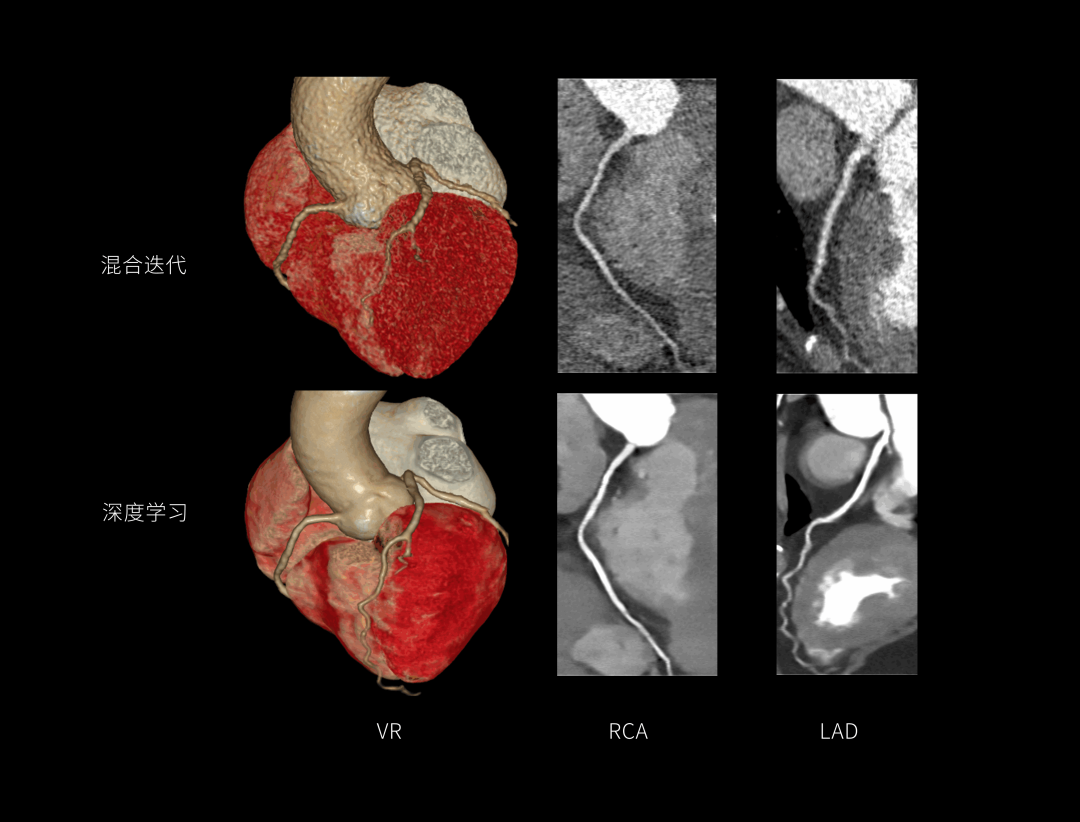

AIIR图像重建提升结果图像可解释性与算法鲁棒性,获得低剂量下的高清成像,超越传统,引领CT成像新标准